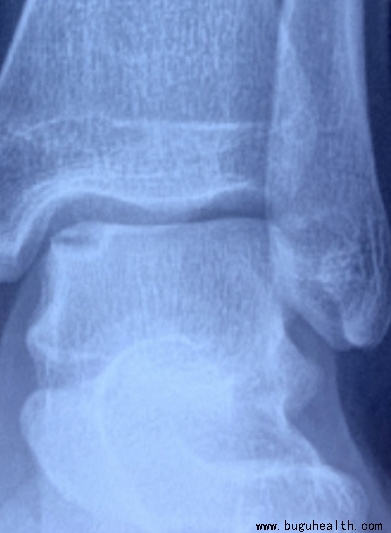

- ����ҽѧ���գ����°����˵ij���ԭ������ƣ� BuGuRMC���ǿ���ҽ������ ��2023-05-05